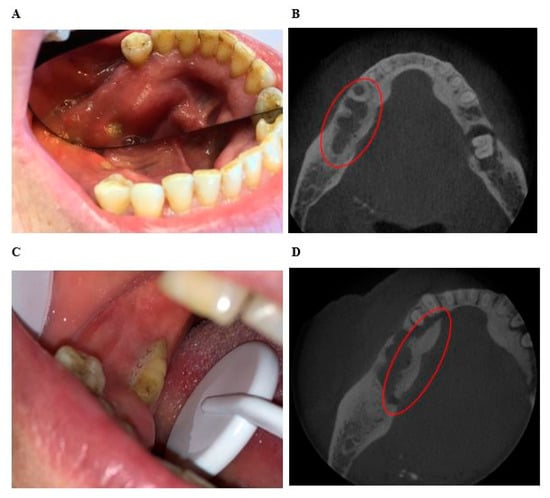

In the “exposed” group, 17 areas (45%) were less extensive clinically than radiologically, 14 areas (37%) were coextensive clinical and radiological, and 7 areas (18%) were more extensive clinically than radiologically (Figure 4 and Figure 5). The median difference between clinical and radiological extent was −1 (IQR [−4;0]). The maximum difference was −8. The clinical extent of osteonecrosis was significantly less than its radiological extent (p < 0.001).

Figure 4.

Example of the difference between the clinical extent and radiographic extent of osteonecrosis determined with CBCT. (A) Mr X: Intraoral view showing bone exposure 7 mm in the region of the left mandibular molar. (B) Mr X: CBCT image of axial section of the mandible, showing bone osteolysis and abnormalities from the incisor region to the left molar region. (C) Mr X: CBCT image of coronal section of the mandible showing bone osteolysis and abnormalities of the inner cortical and cancellous bone of the mandible. The radiological extent seems more important than the clinical extent. (D) Mrs Y: Intraoral view showing bone exposure with pus exudation from the right incisor region to the right molar region. (E) Mrs Y: CBCT image of axial section of maxillary showing dental socket after dental avulsion (green) and intraosseous air bubbles (red). (F) Mrs Y: CBCT image of coronal section of the mandible showing intraosseous air bubbles (red) and periosteal reaction (blue) in the right incisor-canine region. The radiological extent seems less important than the clinical extent.

In the “fistula” group, six areas (67%) were less extensive clinically than radiologically and three areas (33%) were coextensive clinically and radiologically. No area was more extensive clinically than radiologically. The median difference was −2 (IQR [−3; 0]). The maximum difference was −13. In this group, the clinical extent of osteonecrosis was significantly less than its radiological extent (p < 0.031).

The results of this study confirmed that there was a real discrepancy between clinical and imaging, the radiological extent being significantly larger than the clinical extent (Figure 4 and Figure 5). The definition of MRONJ is purely histological and there are no pathognomonic bone signs of MRONJ. Furthermore, denosumab can induced bone reactions that does not lead to MRONJ. However, bones abnormalities used in this study (periosteal reaction, bone osteolysis, bony sequestrum, osteosclerosis, no bone remineralization after tooth extraction, heterogeneous bone condensation, intraosseous air bubble) are radiological arguments in favor of MRONJ. This was confirmed in patients undergoing longitudinal follow-up (Figure 5).